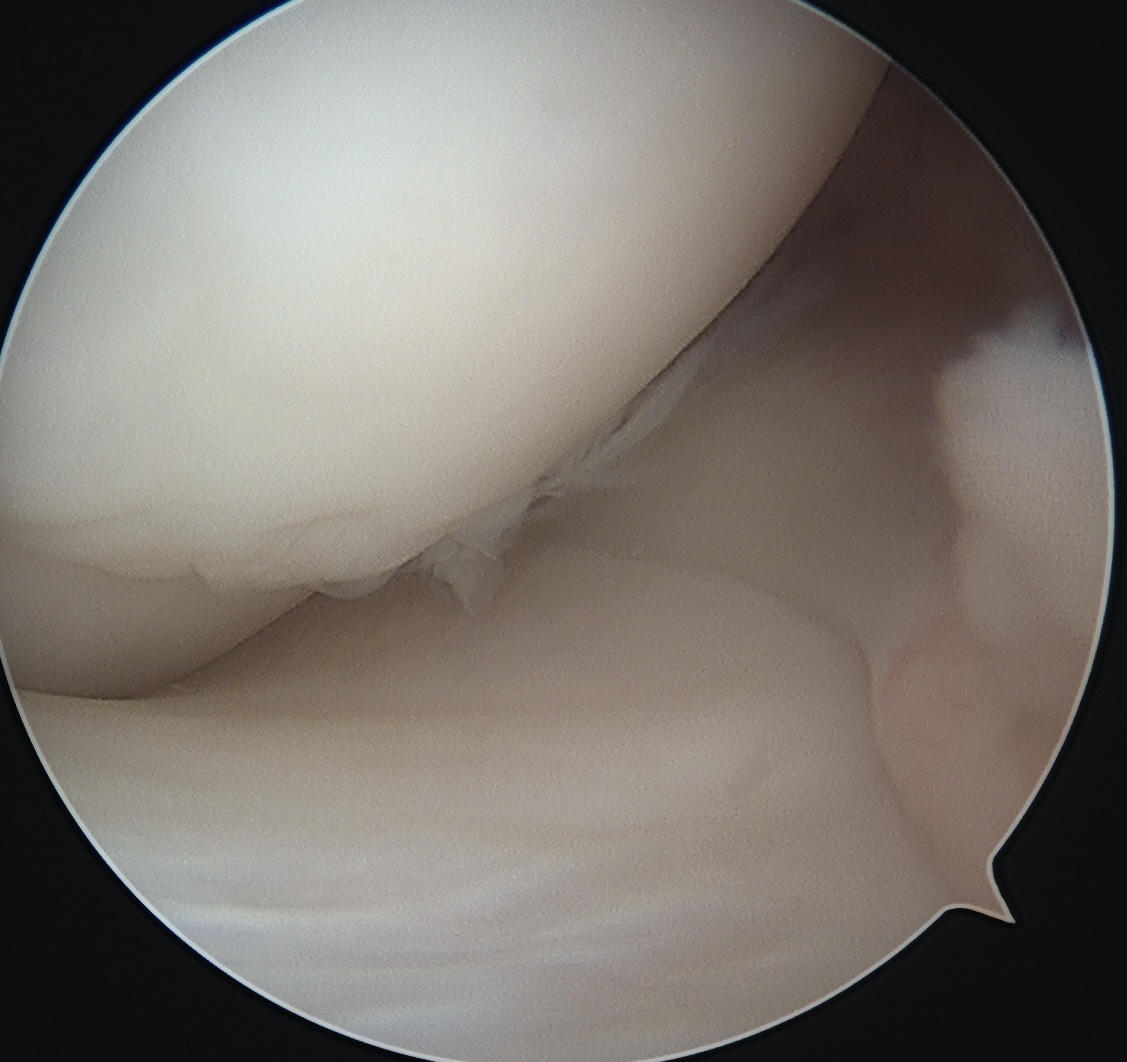

Ensure can see entire dimensions of OCD

- fragment is lateral aspect of the MFC